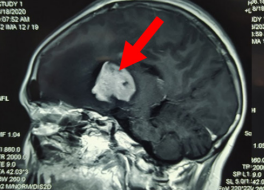

Sốt cao rồi hôn mê, bé trai bị viêm não hoại tử rất hiếm gặp

Viêm não hoại tử cấp tính là căn bệnh rất hiếm, được mô tả lần đầu vào năm 1995 ở châu Á. Bệnh viện Nhi đồng 1 TP.HCM cho biết, đây là trường hợp viêm não hoại tử đầu tiên ghi nhận tại đây.